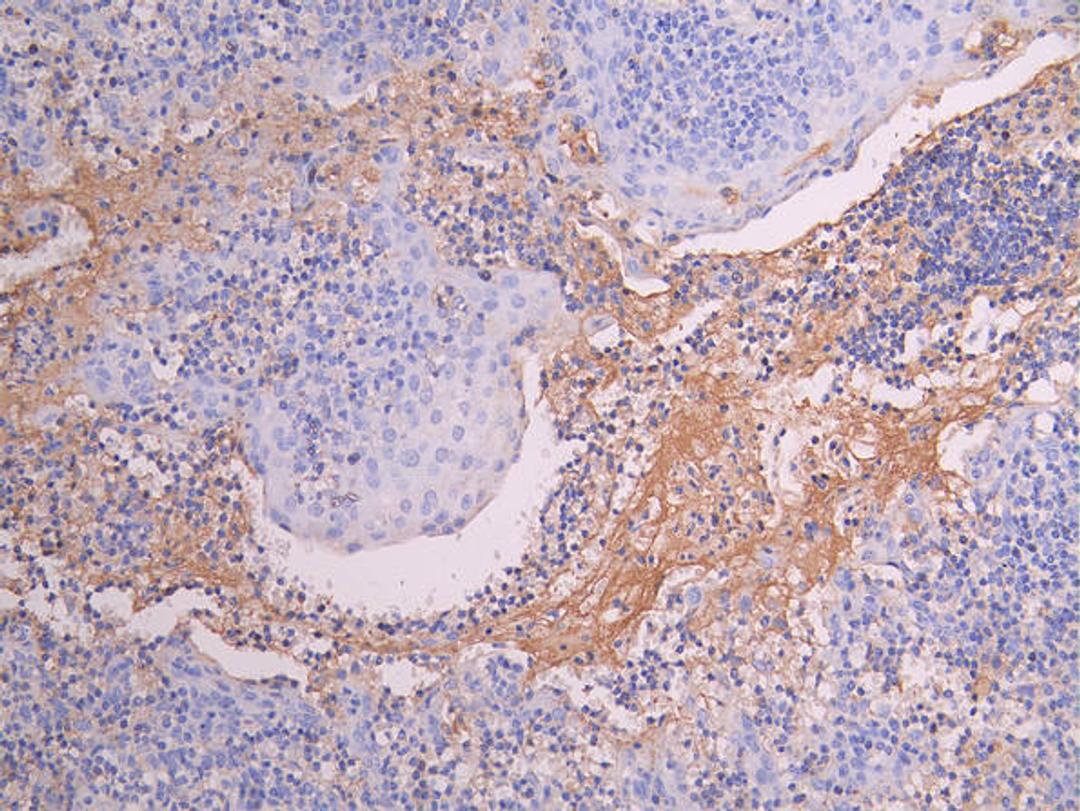

IHC image of CSB-RA014679MA1HU diluted at 1:150 and staining in paraffin-embedded human tonsil tissue performed on a Leica BondTM system. After dewaxing and hydration, antigen retrieval was mediated by high pressure in a citrate buffer (pH 6.0). Section was blocked with 10% normal goat serum 30min at RT. Then primary antibody (1% BSA) was incubated at 4°C overnight. The primary is detected by a Goat anti-human polymer IgG labeled by HRP and visualized using 0.05% DAB.